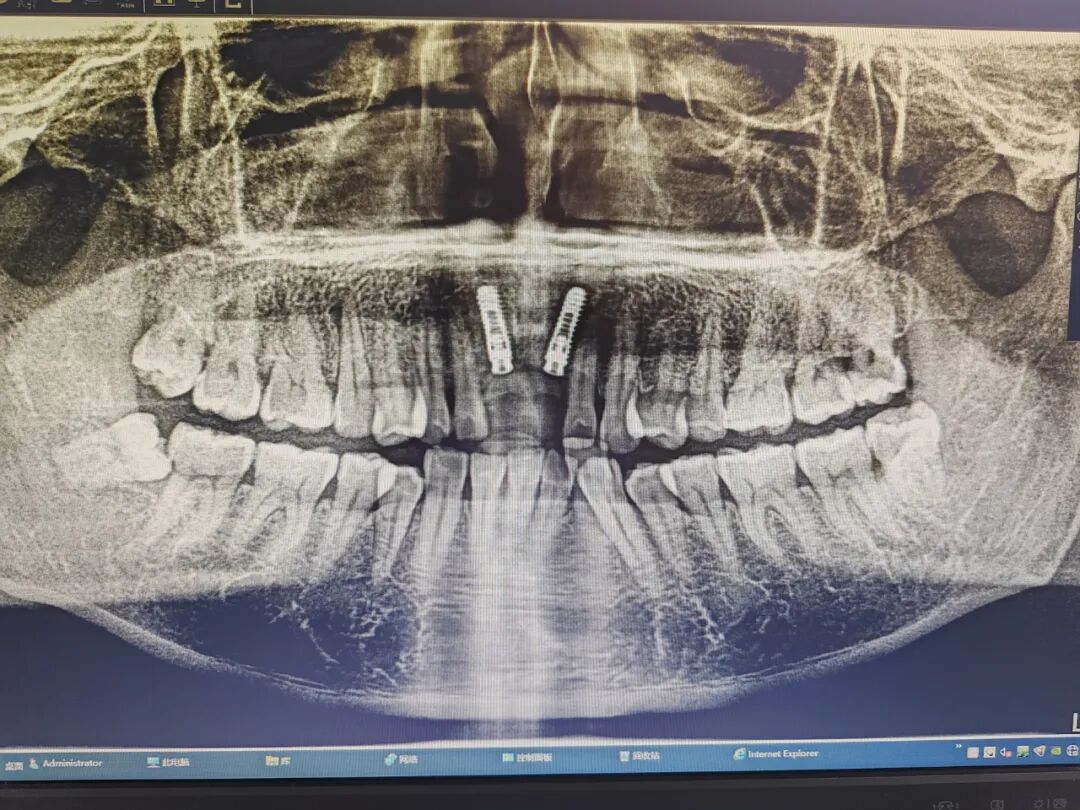

患者杨某,男,52岁,因上前牙缺失两年多,影响美观,就诊于我科决定行种植牙手术。术前CT检查,患者同意我科邰医生种植方案(数字化导板种植方案)。术中微创操作,术后无不良反应,整个疗程约一个小时,过程舒适、安全、精准,术后CT检查,种植体位置精准。